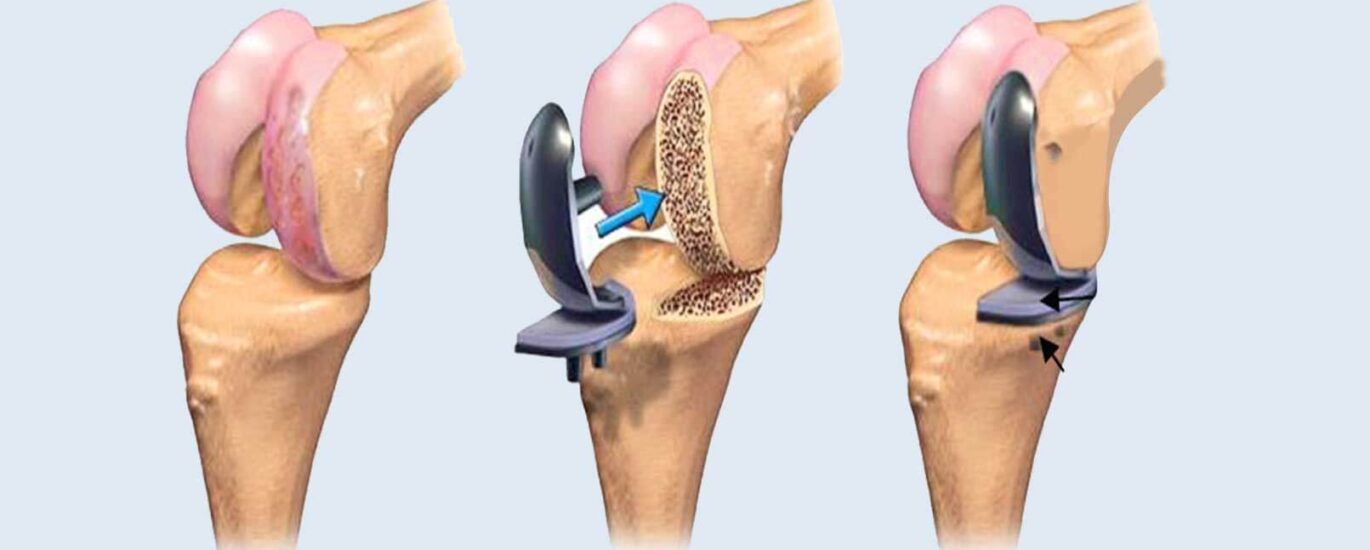

In the landscape of joint reconstruction, artificial implants take center stage due to their simplicity of installation. Arthroscopes are revolutionizing the field by facilitating outpatient surgeries, providing patients with enhanced convenience. Moreover, the integration of advanced tools, including image magnifiers and pre-operative planning systems, is further propelling the evolution of joint reconstruction procedures.